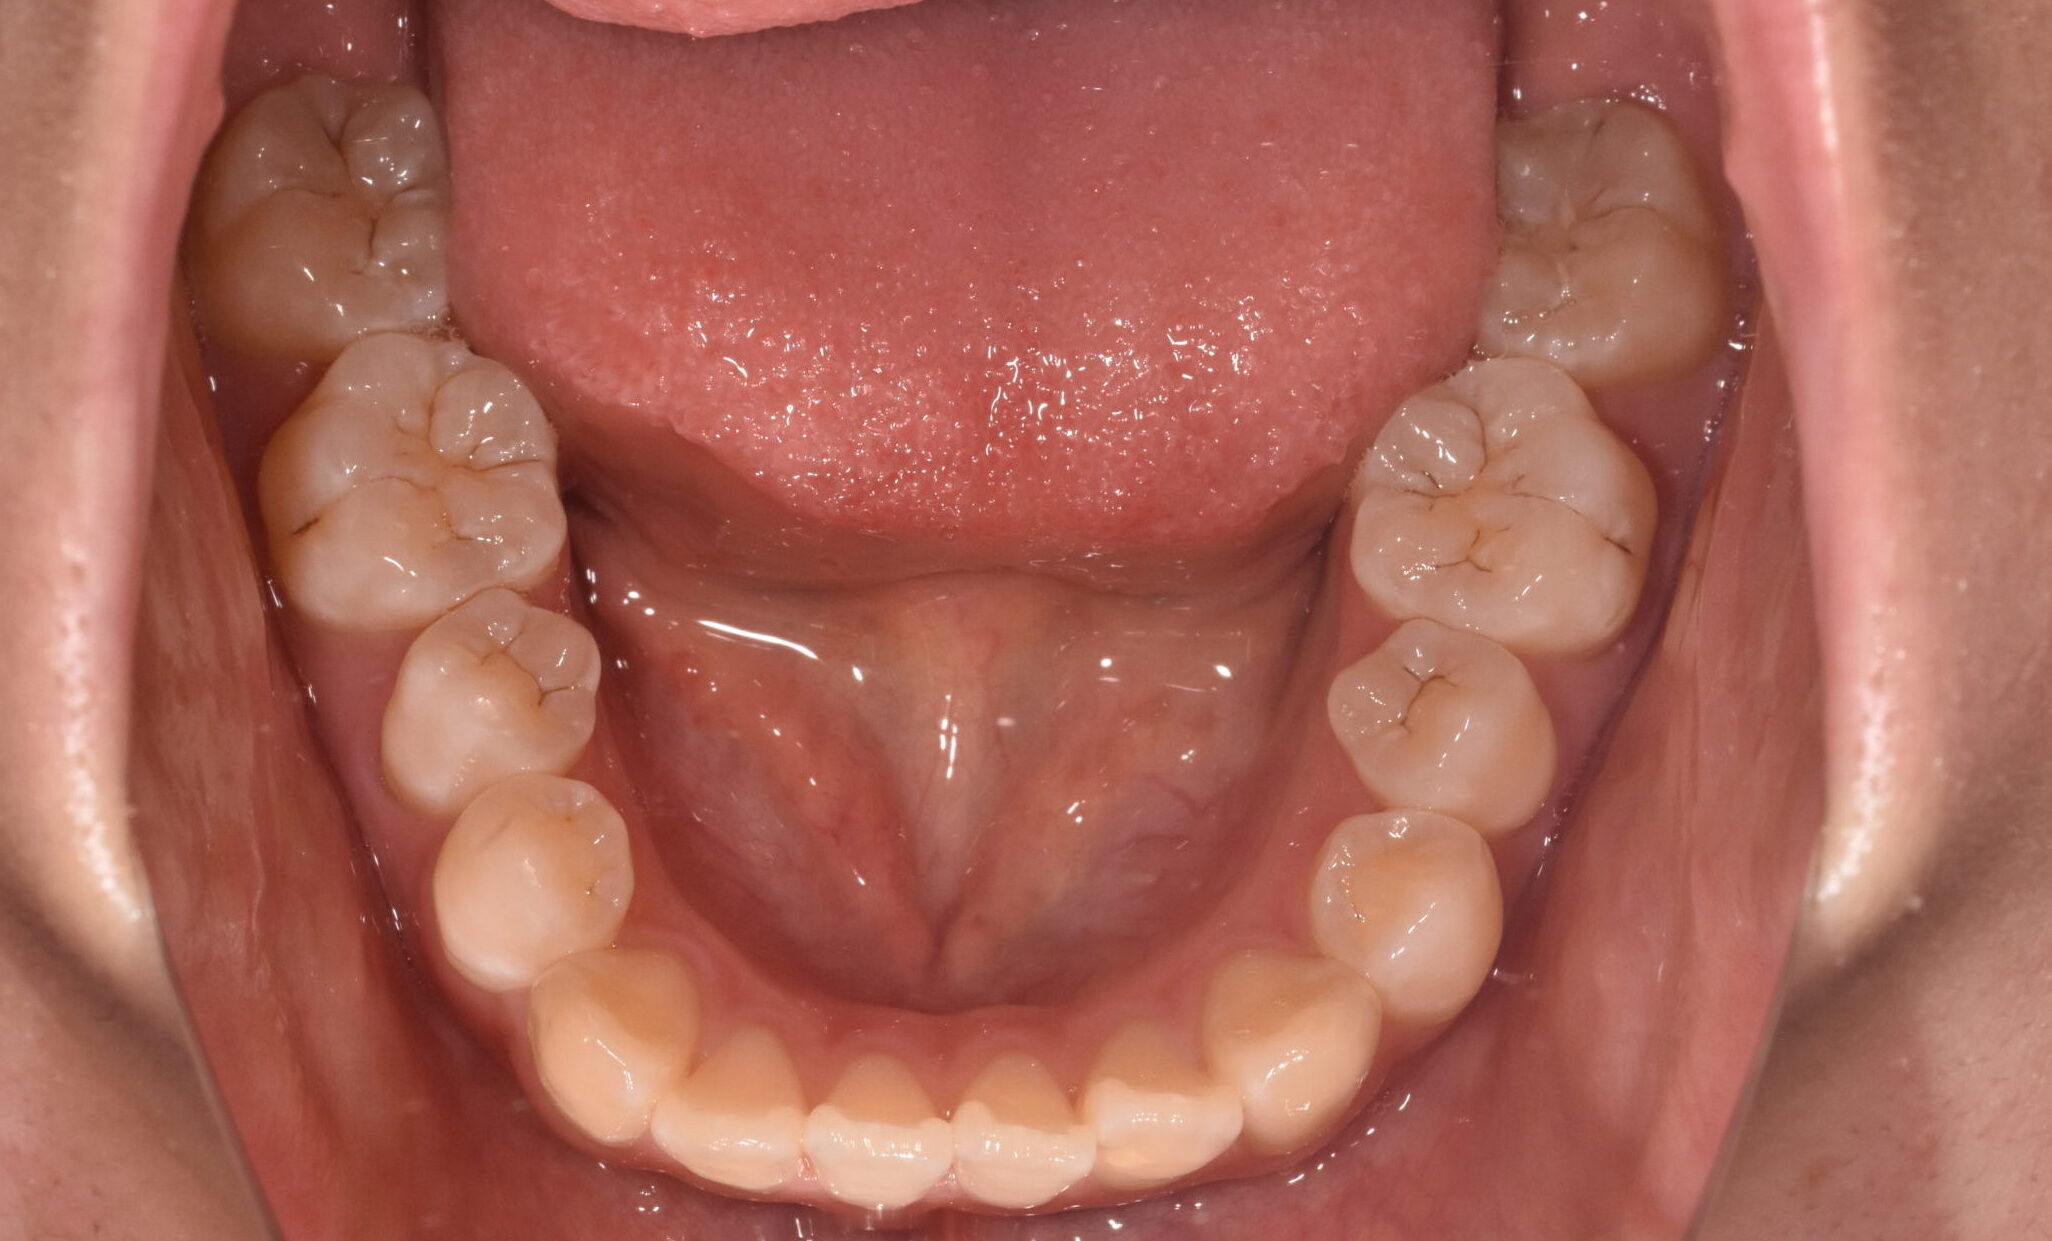

開咬 17歳 女性

治療前

骨格:開咬傾向(前歯が噛みにくいタイプ)

歯並び:前歯が噛み合わない(開咬)+前歯の突出傾向

上下左右の第1小臼歯(4番)を抜歯し、マウスピース型矯正装置を用いて歯並びとかみ合わせの改善を行いました

・抜歯によりスペースを確保し、前歯の位置と角度をコントロール

・マウスピース矯正により、見た目と快適さに配慮しながら治療

・奥歯の高さを調整し、前歯がしっかり噛むように改善

・舌のクセ(舌突出癖)にも配慮し、後戻りを予防